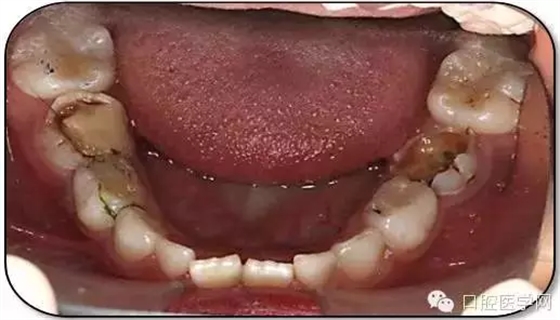

臨床檢查: 75OL齲洞, 舌側(cè)牙體完全劈裂斷端齊齦,探及大量軟化腐質(zhì)。頰側(cè)牙齦紅腫見瘺管,擠壓大量溢膿。叩(±),不松動(dòng)。X線:75根管空虛,牙根吸收約1/2,根尖周及根分歧大面積透射影,35發(fā)育4期,骨硬板尚連續(xù);51殘根,唇側(cè)牙齦瘺管,叩(±),不松動(dòng)。X線:51牙根吸收約1/2,根尖周低密度影。

85O、84DO充填體邊緣不密合,叩(±),不松動(dòng)。84頰側(cè)牙齦略紅腫。X線:84遠(yuǎn)中根及髓室底完全吸收,根分歧透射影,近中根內(nèi)側(cè)見外吸收,44上方骨硬板連續(xù)。85近中根完全吸收,髓室底吸收,根分岐透射影,遠(yuǎn)中根管內(nèi)見根充影像。45發(fā)育4期,骨硬板連續(xù)。

55OL、65OL、74O、53DL齲洞,叩(-),不松動(dòng),齦無異常。

16OL、46OB、26O、36OB窩溝探及淺齲壞,叩(-),不松動(dòng),齦無異常。